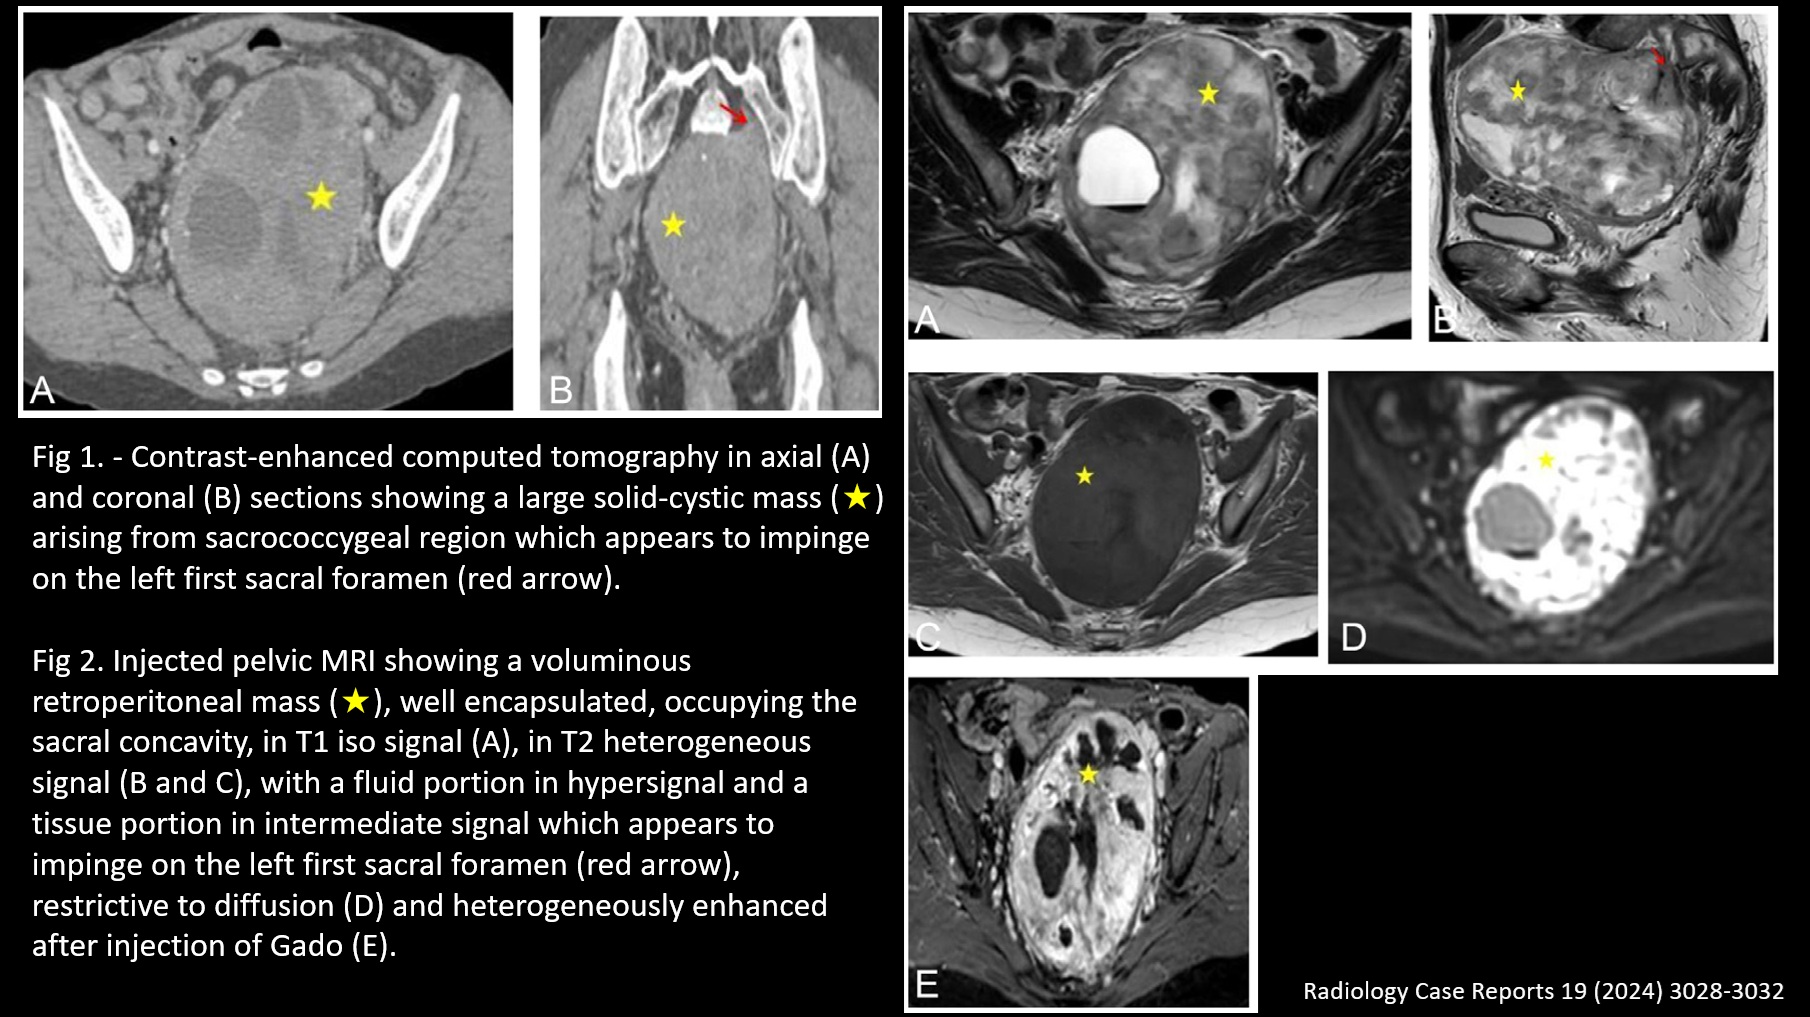

ABDOMEN / Retroperitoneum 57 / M, Abdominal discomfort

| Diagnosis | Pelvic schwannoma | ||

| Keywords | Pelvic schwannoma | ||